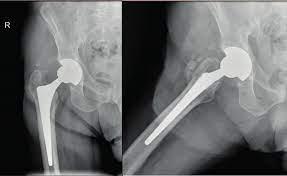

Prosthetic joints are implanted to restore mobility in patients dealing with arthritis, trauma injury, or bone diseases affecting major joints like knees, hips, and shoulders. However, implants come with the risk of surrounding tissues becoming infected due to bacteria entry during or after surgery. If left untreated, prosthetic joint infections can cause implant failure and necessitate revision surgery. Market players offer antimicrobial coatings, bactericidal joint liners, advanced dressings and wound drainage systems, antibiotic and antiseptic agents to minimize risk at hospitals and for long-term care.

The prosthetic joint infection market is witnessing rising demand for anti-microbial coating technologies for implants. Advanced silver, antibiotic and polyhexamethylene biguanide coatings help reduce bacterial colonization on the implant surface and entry points. Major players are gaining FDA clearances for novel biomaterials that prevent initial attachment of pathogens. With joint replacement volumes growing among younger more active populations, demand is increasing for long-term infection preventive solutions integrated into the implant design.